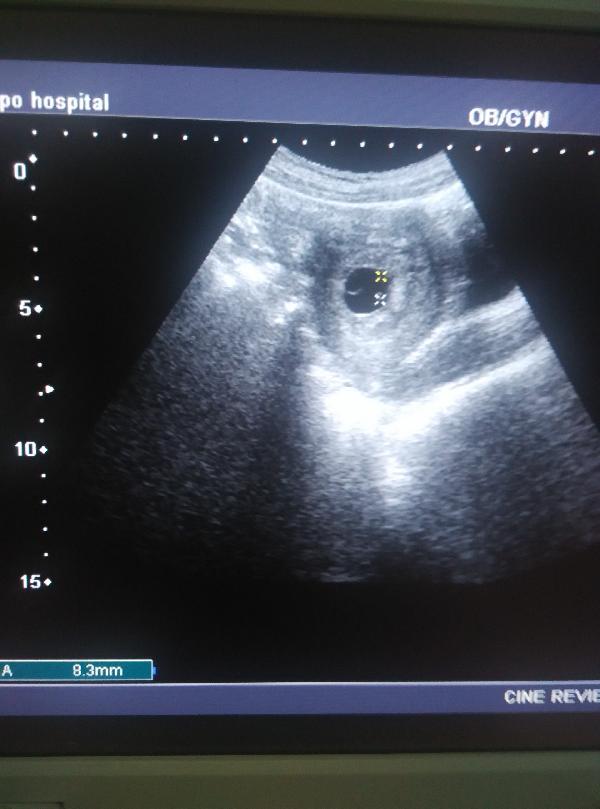

听了我详细的解答,海凤同意做经阴道的超声检查了,结果回报:早孕6+周,可见胎心。

But付虹医生温馨提示:因为经腹部超声最早观察到妊娠囊约在末次月经后6周,经阴道超声最早在末次月经后的4周2天就可以观察到直径1~2mm的妊娠囊,所以只要您停经的天数够长、腹部不太胖、憋尿足够,依然可以从腹部超声看清楚怀孕的情况。